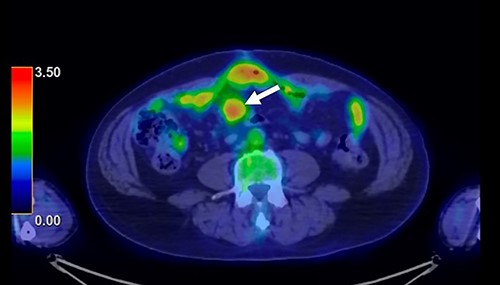

A 62-year-old man underwent distal gastrectomy for gastric cancer. The pathological diagnosis was pT3N0M0 Stage IIA according to the TNM Classification of Malignant Tumors, 8th Edition. In our hospital, follow-up chest and abdominal CT are performed every 6 months for 5 years after gastrectomy. About 2 years later, follow-up CT scan revealed a mesenteric tumor. CT also showed the absence of the other evidence of recurrence of the gastric cancer, such as ascites, distant metastatic tumor and remnant gastric tumor (Fig. 1). The mesenteric tumor had not been identifiable on previous images after gastrectomy; thus, this image was the first image on which GIST was identified. Positron emission tomography (PET)-CT was performed to evaluate the mesenteric tumor and identify other tumors, showing that the maximum standardized uptake value (SUV max) of the mesenteric tumor was 2.9, with no other tumors present in the entire body (Fig. 2). The mesenteric tumor was deemed to be a resectable tumor such as a GIST, desmoid tumor or malignant lymphoma, and not peritoneal dissemination because CT and PET-CT revealed no other tumors.

PET-CT finding. PET-CT showed that the maximum standardized uptake value (SUV max) of the mesenteric tumor was 2.9, with no other tumors present in the whole body.

In the present case, PET-CT was particularly helpful for distinguishing GIST from recurrence after gastrectomy for gastric cancer. Discussions about the differences in the SUV max on PET-CT between GISTs and metastatic tumors of gastric cancer are rare. Fluorodeoxyglucose-PET is reportedly useful for diagnosing recurrent gastric cancer, and the median SUV max of recurrent disease was ≥4.0 [11, 12]. However, Iwamura et al. reported that the SUV max of GISTs with a low mitotic index was significantly lower (2.4 ± 4.2) than that of GISTs with a high mitotic index (9.6 ± 7.6), indicating that the SUV max reflects the cell proliferation of GISTs [13]. These studies suggest that the SUV max of GIST with a low mitotic index might be lower than that of metastatic tumors of gastric cancer.

In the present case, the SUV max of the mesenteric tumor was 2.9, and there was no other metastatic tumor in the whole body. The low SUV max and presence of a single tumor indicated that tumor was a resectable tumor. After the diagnosis, we performed laparoscopic surgery. Observation with a laparoscope showed a mesenteric tumor at the small bowel, with no metastatic tumor. In advanced gastric cancer, staging laparoscopy is frequently performed to assess the gastric tumor and metastatic lesions, particularly in cases with peritoneal deposits [14]. Staging laparoscopy avoids unnecessary laparotomy and the morbidity of the laparotomy is minimal. In the present case, laparoscopic surgery was useful for estimating the resectability of the tumor and checking for peritoneal dissemination and other metastatic tumors.